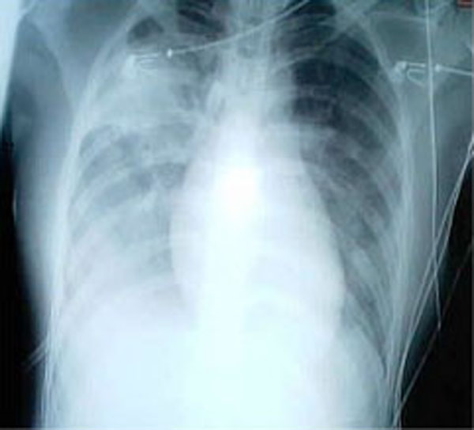

- CXR: Bilateral infiltrates, features of atypical pneumonia